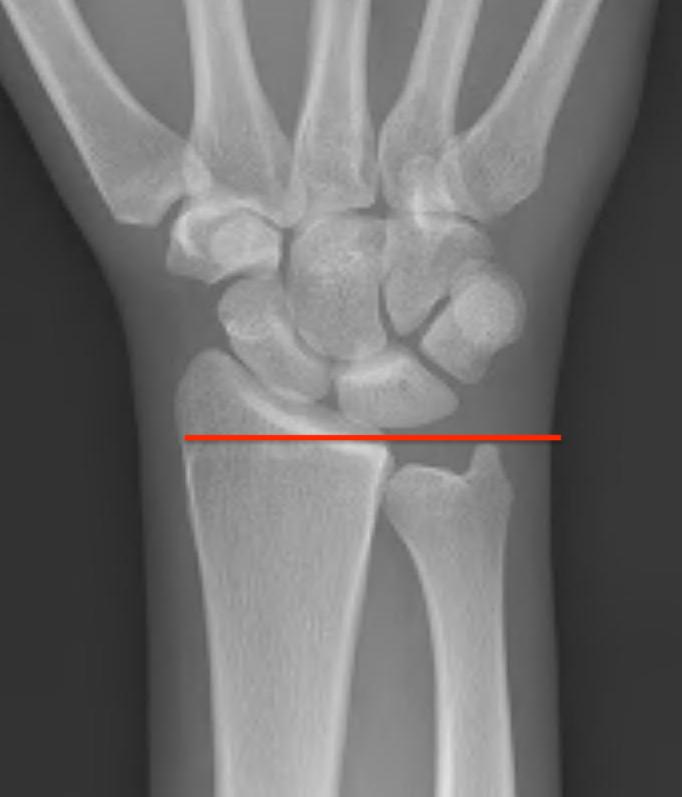

Ulna variance

Supination and pronation alter variance

- varies up to 3 mm with wrist position

- pronation increases ulnar variance

- supination decreases variance

90 / 90 view

- zero rotation view

- neutral supination / pronation

- PA film with wrist in neutral

- elbow 90° / shoulder abducted 90°

Line from lunate fossa and ulna head

- wide variation in population

- mean ulna variance is 1 mm (range 2 - 4)

Ulna neutral

Ulna positive

Ulna negative